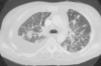

Fig. 1. Radiografía posteroanterior de tórax.

Mujer de 34 años de edad, con antecedentes de lupus eritematoso de complicado control que obliga a un tratamiento prolongado con dosis altas de corticoides. Presenta clínica de un mes de evolución de astenia, tos y febrícula con sudoración profusa en los últimos 10 días, que evoluciona con deterioro progresivo y disnea de reposo.